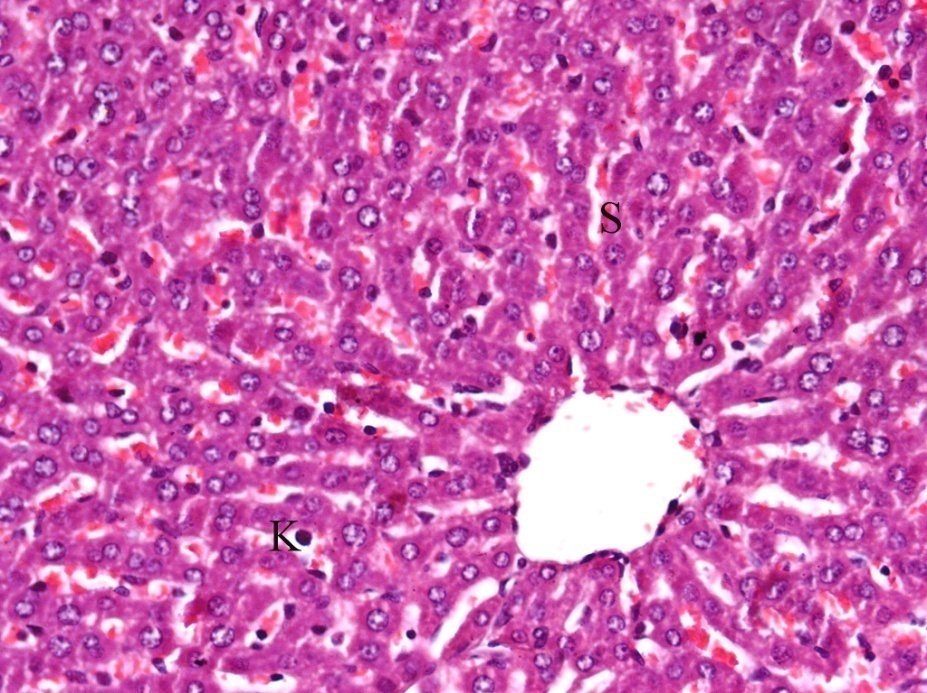

Normal structure of the hepatocytes, central vein, sinusoidal spaces and prominent nucleus were observed in the liver section of control rats (fig. 2). Cisplatin exposure caused marked damage to hepatocytes in the form of degeneration, cytoplasmic vacuolation, centrilobular necrosis associated with mononuclear cells infiltration around central vein and the central vein was enlarged and congested. The sinusoid walls showed numerous Kupffer cells, hemorrhages with sinusoids dilatation, and nuclei are pyknotic with condensed chromatin (fig. 3).

Fig. 3: It shows photomicrograph of section from liver of cisplatin (H and E X 400)

In the group received ginger and carrier showed nearly normal structure with few Kupffer cells and hemorrhage blood sinusoids (fig. 4 and 5).

Fig. 4: It shows photomicrograph of section from liver of Carrier group (H and E X 400)